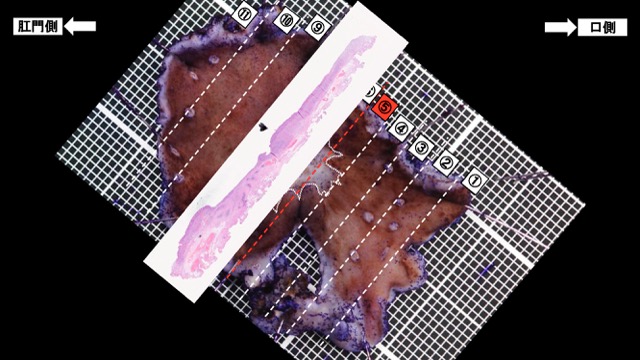

胃012